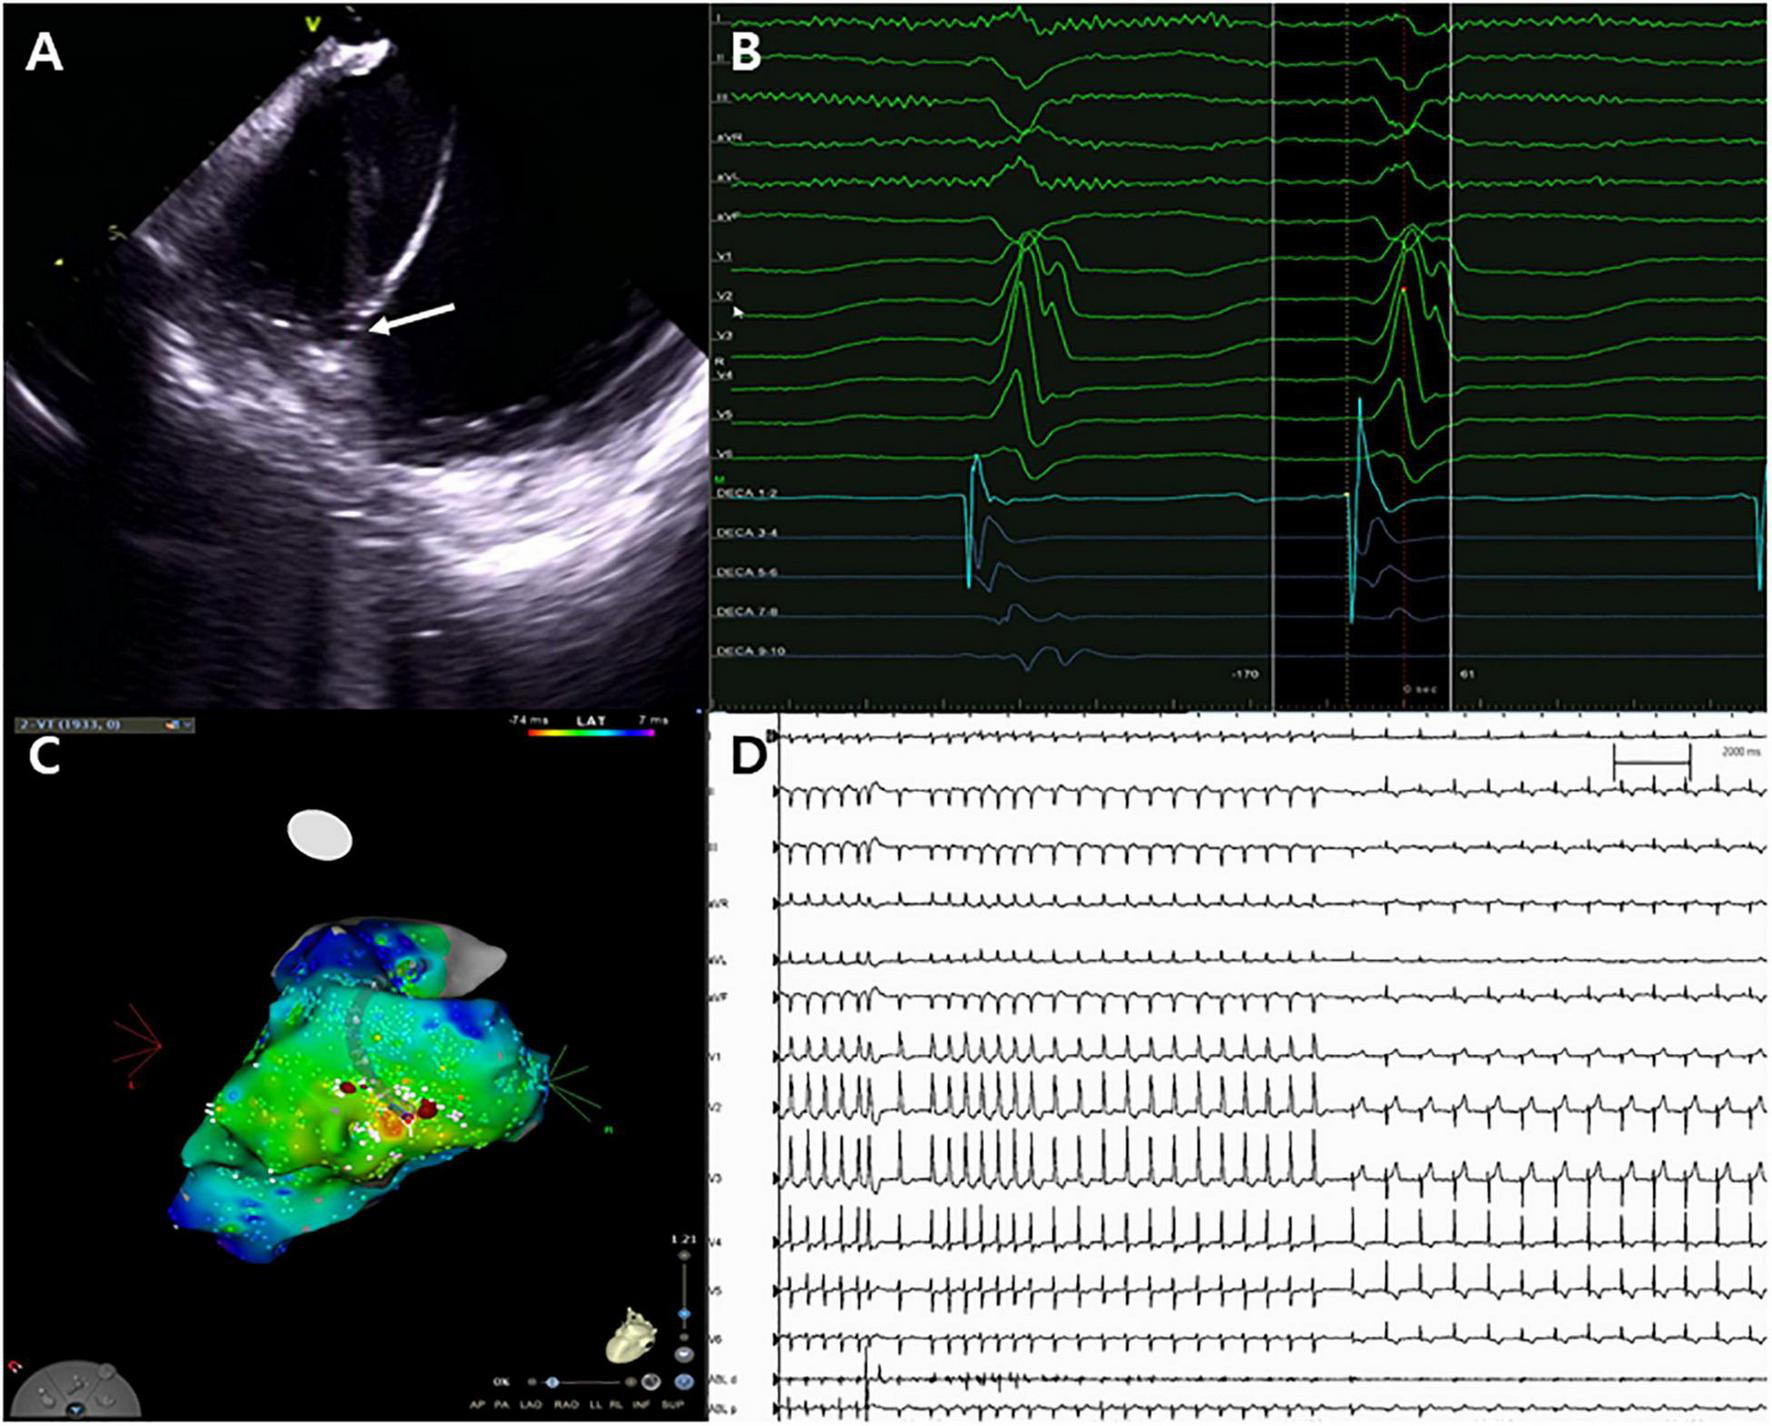

FIGURE 2

Catheter ablation for ventricular tachycardia. (A) Successful ablation site on the left posteromedial papillary muscle (white arrow). (B,C) Unipolar Q signal on successful ablation site and three-dimensional activation map. (D) Termination of ventricular tachycardia with steam pops.

Following admission to the cardiac intensive care unit, the patient underwent a percutaneous left-sided stellate ganglion block with bupivacaine, a cardiac sympathetic intervention suppressing sympathetic activity for controlling VT. However, the cardiac sympathetic intervention was unsuccessful. Given that the VT remained unresolved and the driving cause of electrical instability was unclear, radiofrequency catheter ablation was decided as the most appropriate treatment strategy. Endocardial electroanatomical mapping of the LV using a CARTO-3 system (Biosense Webster) was performed through both transseptal and retroaortic approaches using a multi-electrode catheter. The procedure was performed using intracardiac echocardiography (ICE) through a transseptal approach and viewing the LV structure in real-time. The ablation catheter was positioned through the retroaortic approach. During endocardial mapping, intracardiac electrograms showed fractionated potentials around the posteromedial papillary muscle with the earliest activation (−40 ms) (Figures 1B–D). Endocardial bipolar voltage mapping revealed no scarring (0.5–1.5 mV), and the activation map was consistent with an exit site in the posteromedial papillary muscle region. Under direct ICE visualization (Figure 2A), endocardial ablation using an irrigated-tip catheter (SmartTouch, Biosense Webster) and 40 W was applied to target the earliest site that showed the initial Q wave in the unipolar signal with 10–15 g of contact force (Figures 2B,C). During the first ablation, the VT was terminated for 30 s with an inaudible steam pop recorded by ICE (Figure 2D and Supplementary Video 1), and a sudden rise in electrical impedance was not noted. After confirming that no evidence of perforation or tissue defects were present in the first ablation site, multiple circumferential ablations were performed in the area surrounding the posteromedial papillary muscle without further steam pops. Repeated programmed electrical stimulation failed to induce VT following the ablation. Before the end of the procedure, the ICE operator confirmed that there was no evidence of procedure-related complications. The transthoracic echocardiography performed the next day showed no evidence of mitral regurgitation or tissue defects in the ablation sites (Figure 3A).